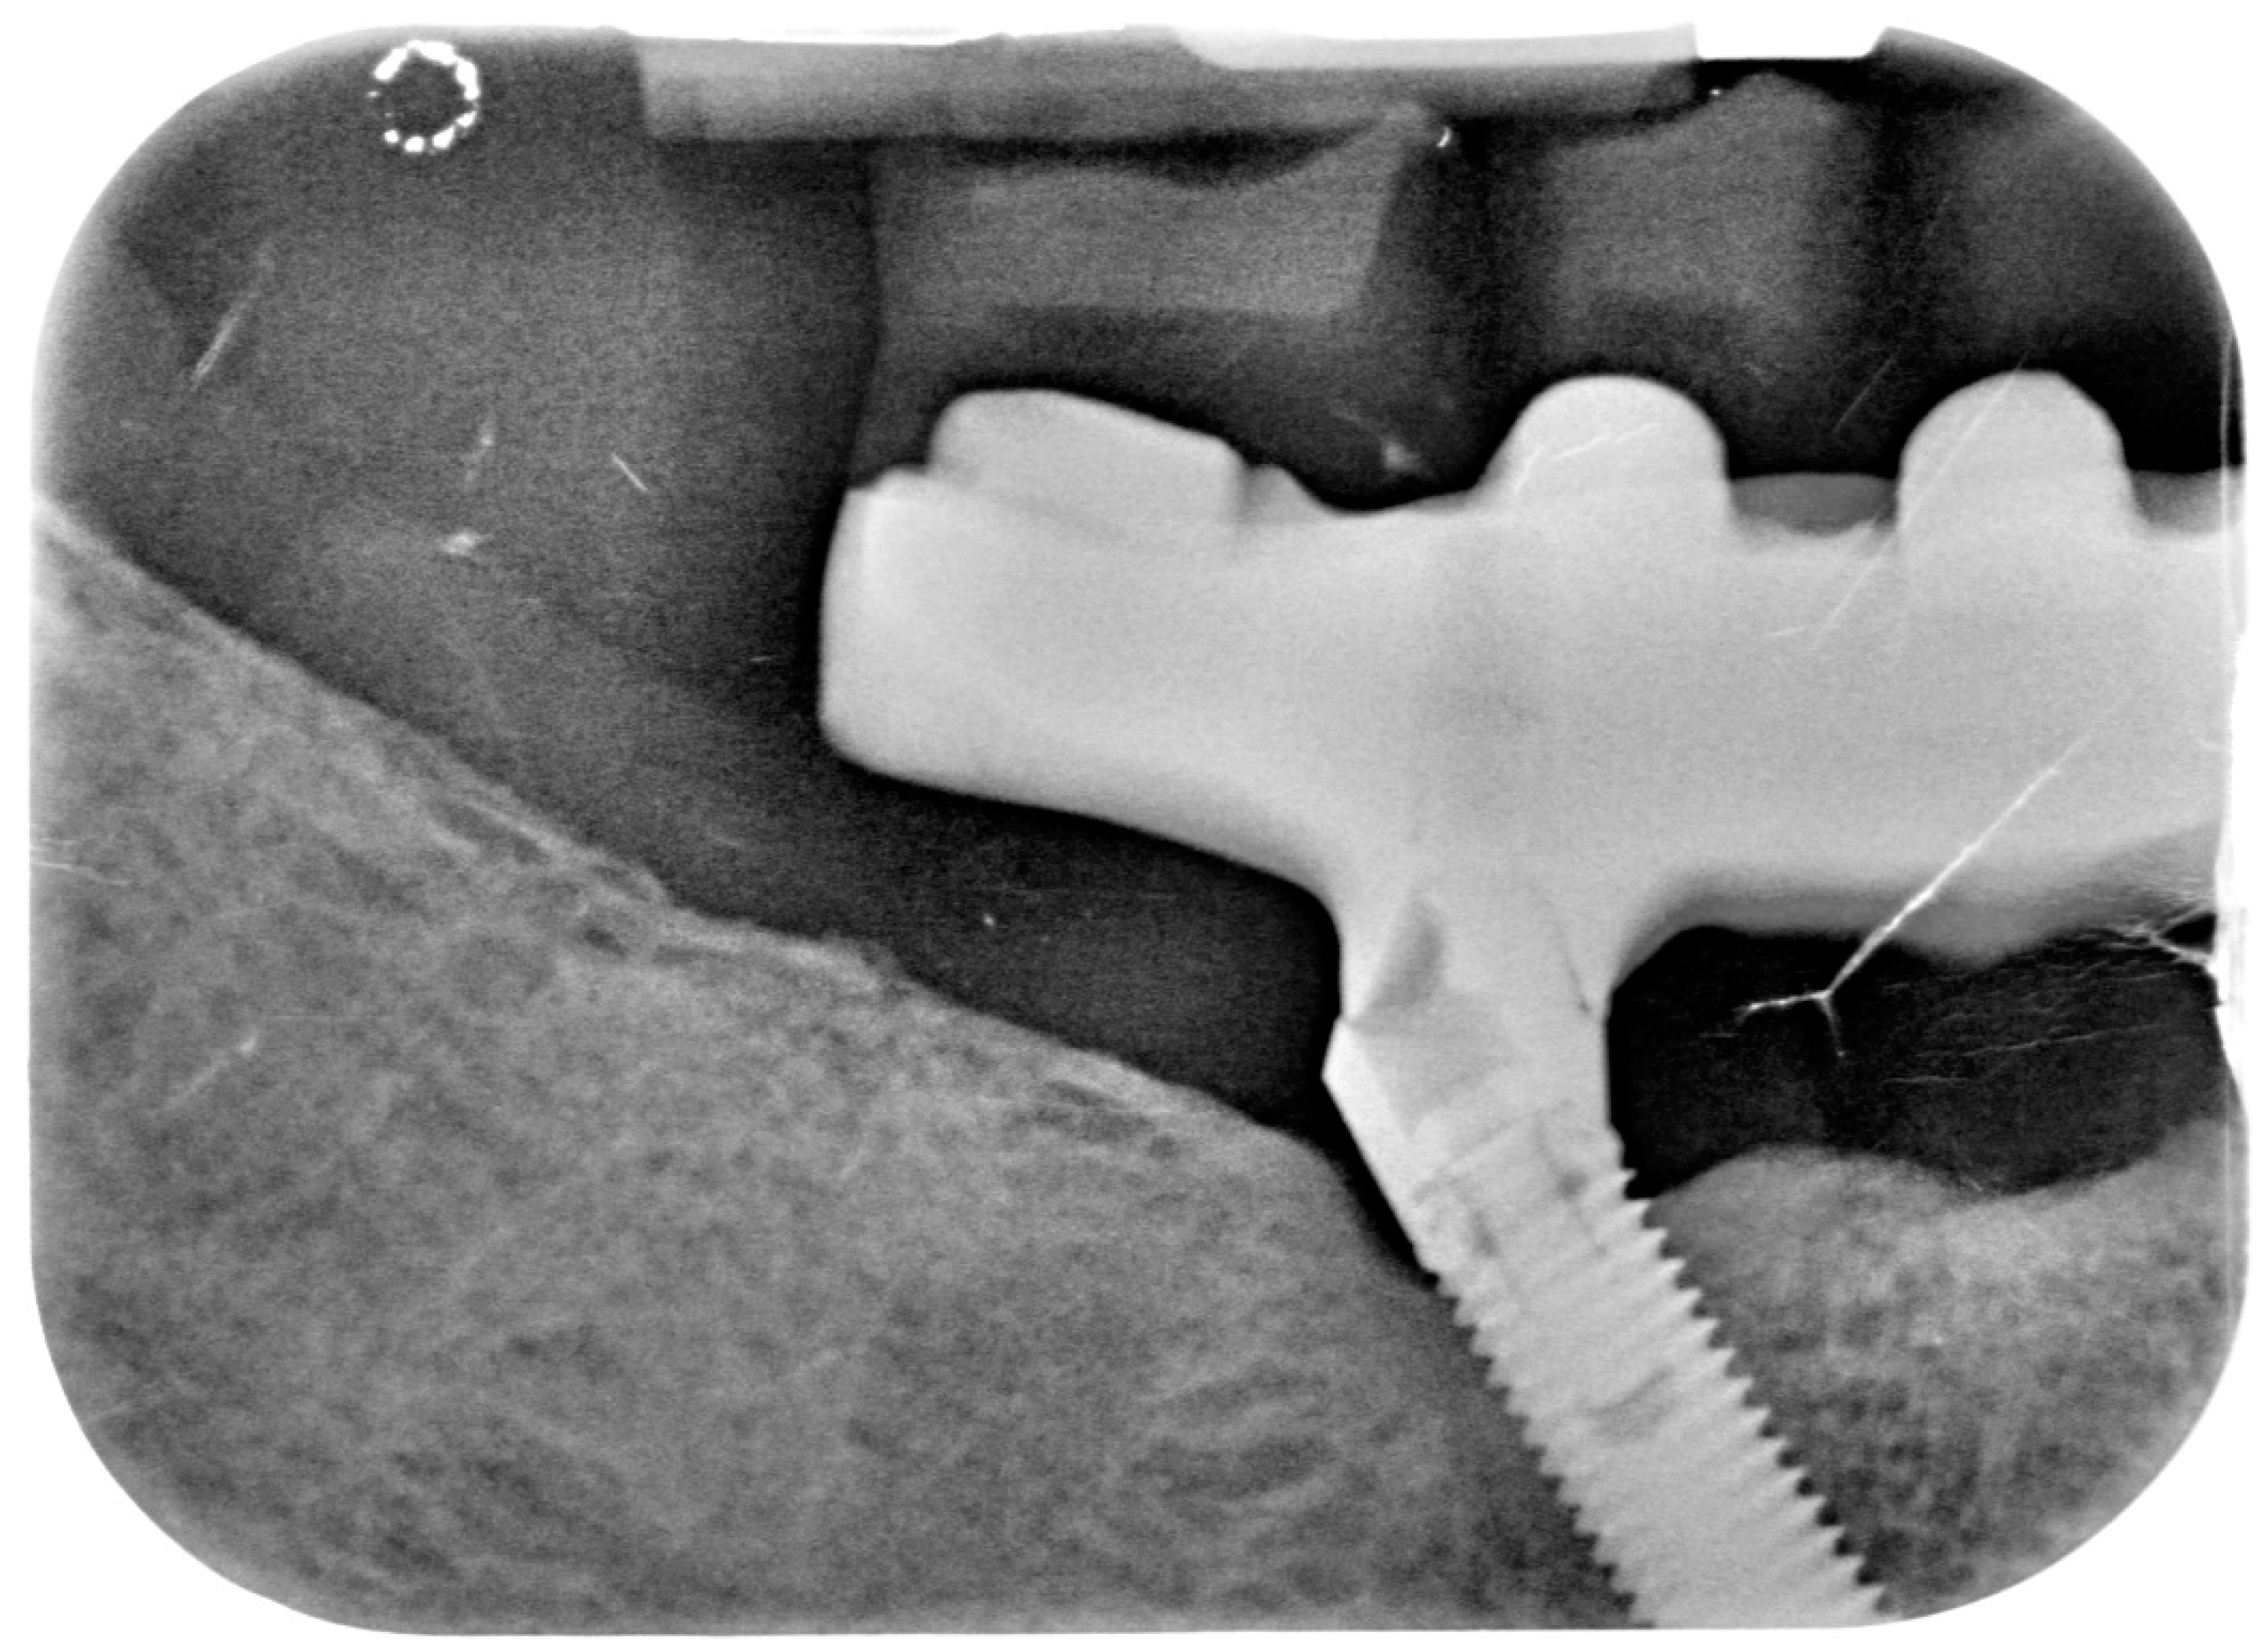

After removing the prosthetic rehabilitations, diagnosis of the soft tissue was done. Peri-implant assessment (PPD, TL, BI, PI, and mobility) and, subsequently, assessment of color, contour, consistency of soft tissues was performed. Individual oral hygiene instructions including re-education and motivation if needed was done. Bidimensional radiographic assessment (with periapical and panoramic radiograph) was performed (Figure 10 and Figure 11).

Figure 11.

X-ray of 4.5 dental implant in patient before treatment.

The clinical assessment allowed finding a probing depth of 6 mm mesial/circumferentially to 3.5 with bleeding in the two lower jaw distal implants and a probing depth of 4–2.5 mm mesial/circumferentially with bleeding in the two lower jaw central implants. In the upper jaw, a probing depth of 1–2 mm was found. None of the implants showed mobility.

A bidimensional radiographic assessment of the lower jaw and upper jaw implants (with periapical and panoramic radiograph) was done. In the lower jaw implants, a concave bone resorption can be observed of about 4 mm mesial and distal to both distal implants (3.5 and 4.5). No bone resorption was revealed on the two lower jaw central implants and on the four implants positioned in the upper jaw.